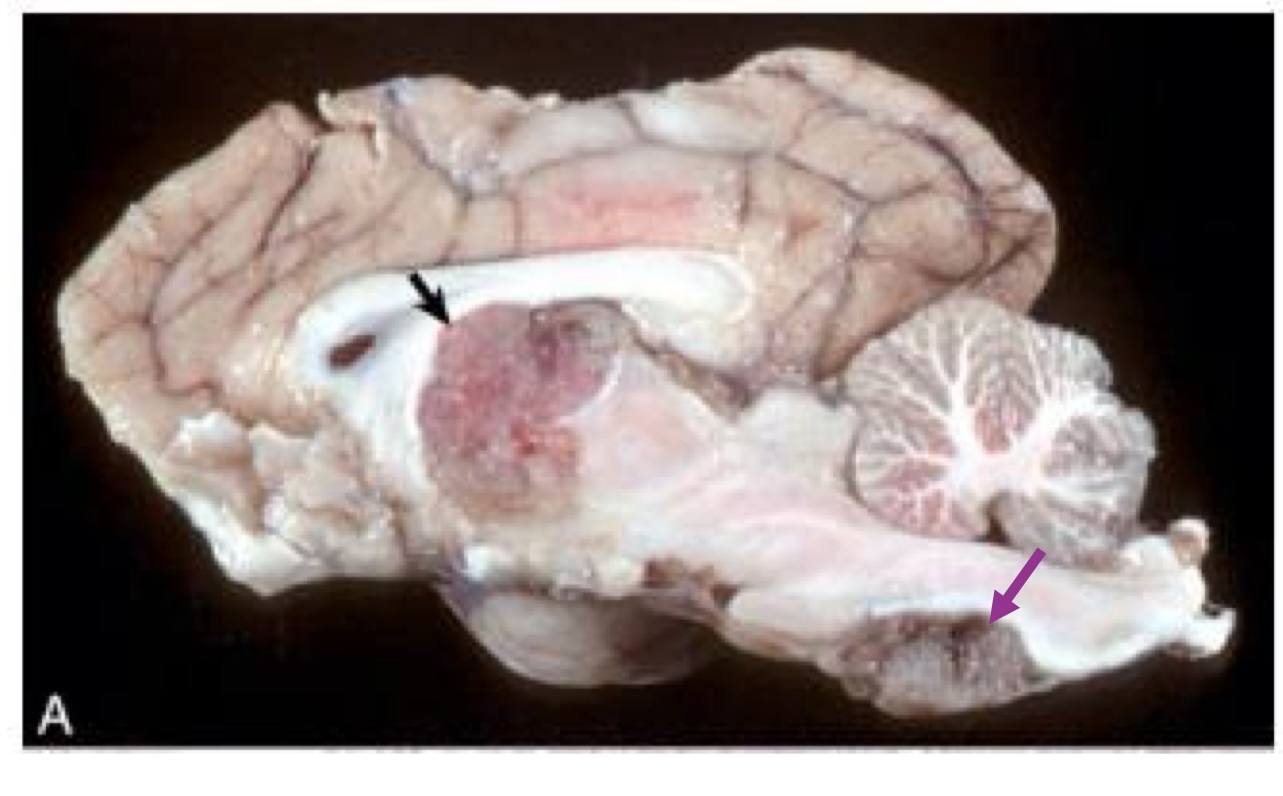

what is this?

equine protozoal myeloencephalitis → large focus of hemorrhage and necrosis in the caudal brain stem caused by sarcocystis neurona